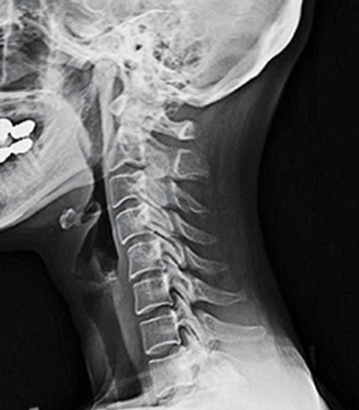

건강한 척추는 척추뼈(척추의 뼈)가 곧고 중립적인 정렬로 겹겹이 쌓인 것으로 구성되며, 경추는 척추의 가장 윗부분을 말합니다.

경추는 처음 7개의 척추체(C1~C7)로 구성되어 있으며 뼈, 추간판, 인대, 힘줄 및 신경의 복잡한 네트워크입니다.

앞서 언급한 바와 같이 목의 자연적인 전만증은 경추를 안쪽으로 C자 모양으로 굽게 하는데, 그 곡률 정도가 20~40도 범위에 속하면 정상적이고 건강한 경추 전만증의 범위로 볼 수 있습니다. 만약 사람이 경추 전만증의 상실을 경험하고 그 정상 범위에 속하지 않는다면 이는 목이 지나치게 곧게 되었다는 것을 의미합니다.

건강한 척추는 앞에서 보면, 뒤에서 보면 곧게 보이고, 옆에서 보면 부드러운 'S'자 모양을 이룬다. 이는 척추의 자연스럽고 건강한 곡선 때문입니다.

후만증은 흉추에 영향을 미치는 역 'C' 모양의 척추의 자연적인 바깥쪽 굽힘을 의미하며, 전만증은 경추 및 요추 부분에서 표준 'C' 모양의 척추의 자연적인 안쪽 굽힘을 나타냅니다.